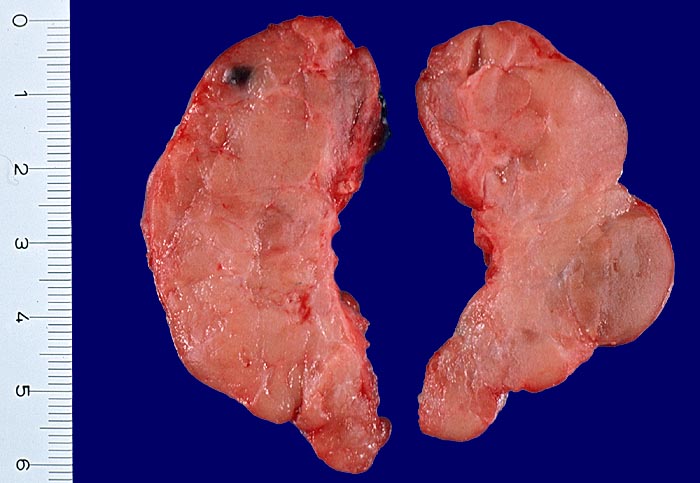

Hashimoto Thyreoiditis

Systemerkrankung/Immunpathologie

Schilddrüse

Endokrinium

Aufgrund der Entzündungsinfiltrate auffallend helles knotiges Schilddrüsenparenchym. Die Drüse ist kaum vergrössert.

Makroskopie